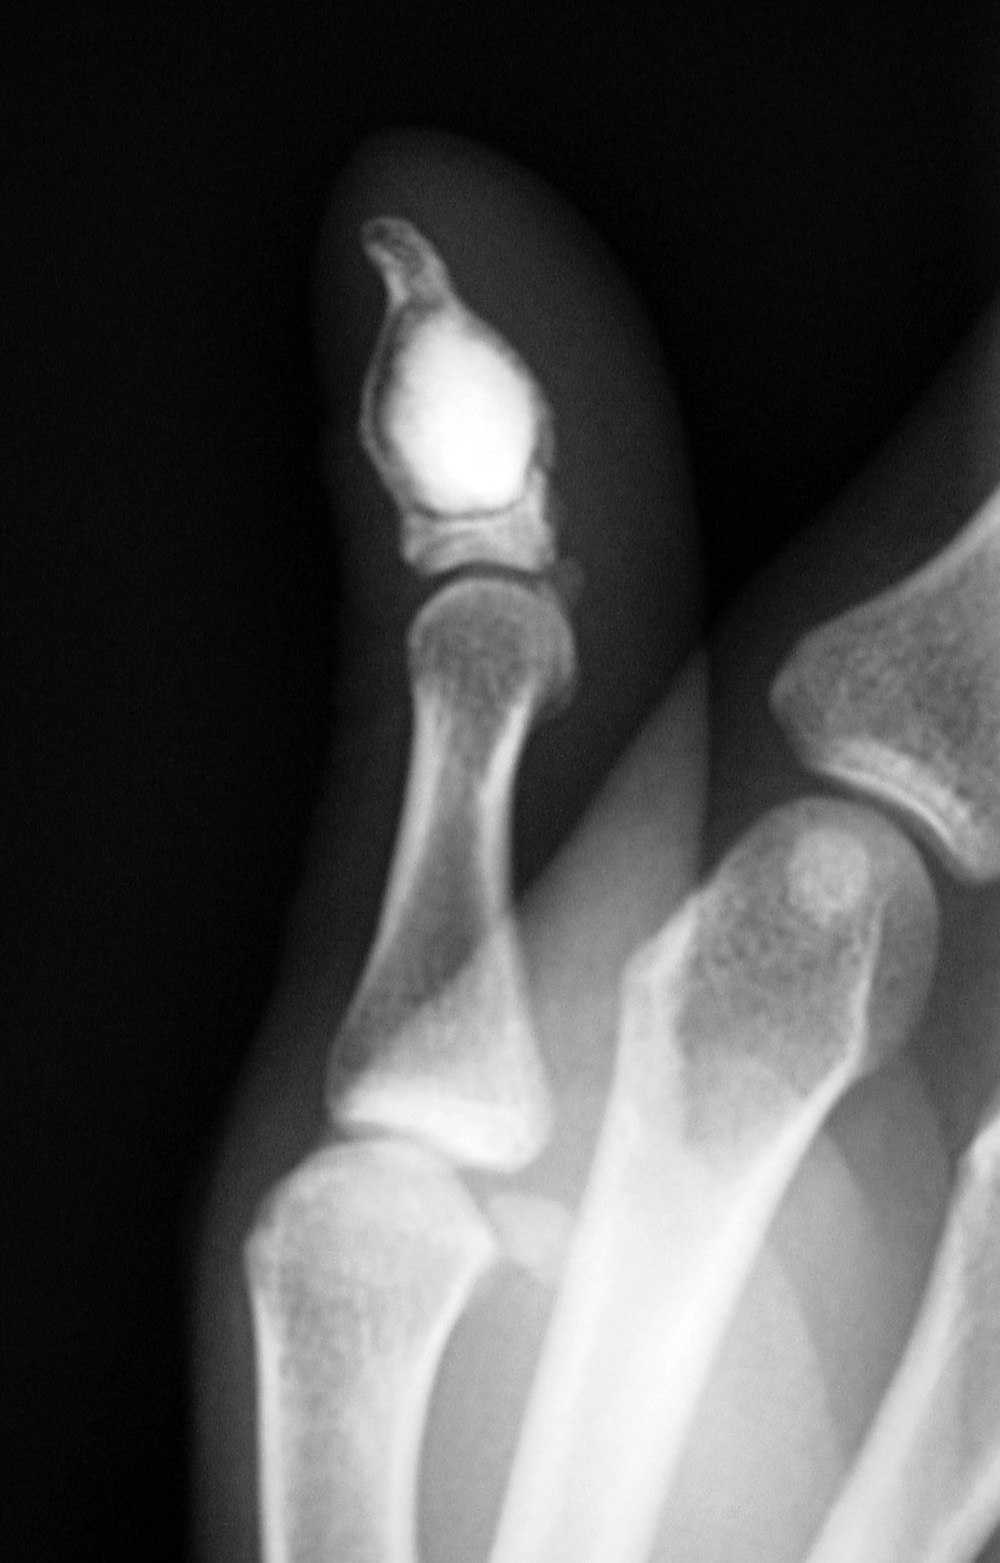

Patient with enchondroma in distal phalanx of the thumb which has been curetted and filled with a bone substitute.